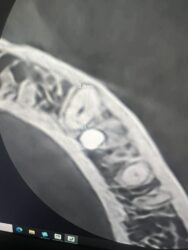

I have this implant case for tooth #28. I am worried about the anterior loop of the IAN here. It looks like it terminates at slice 62 and 63 but then I have a circular radiolucent area in slice 65. Do you think this is still the mental? If so I have about 10mm from the crest of the ridge. Do you think I’d be safe with an 8 mm implant here?

Just looking at what you provided it looks like there is sufficient room for an 8mm implant and that other slice I believe around 65 just looks like a void around the bone that looks similar to the pano version of the cbct and doesn’t present in other slices, nerve appears to be below that area.

Here are some screenshots of the CT for the case I am planning. Should I be concerned about the circular radiolucent area below 22 on page 2? When I traced it back I only saw it in a few segments. I remember Ivan saying there could be anterior branches of the IAN or vasculature in this region.